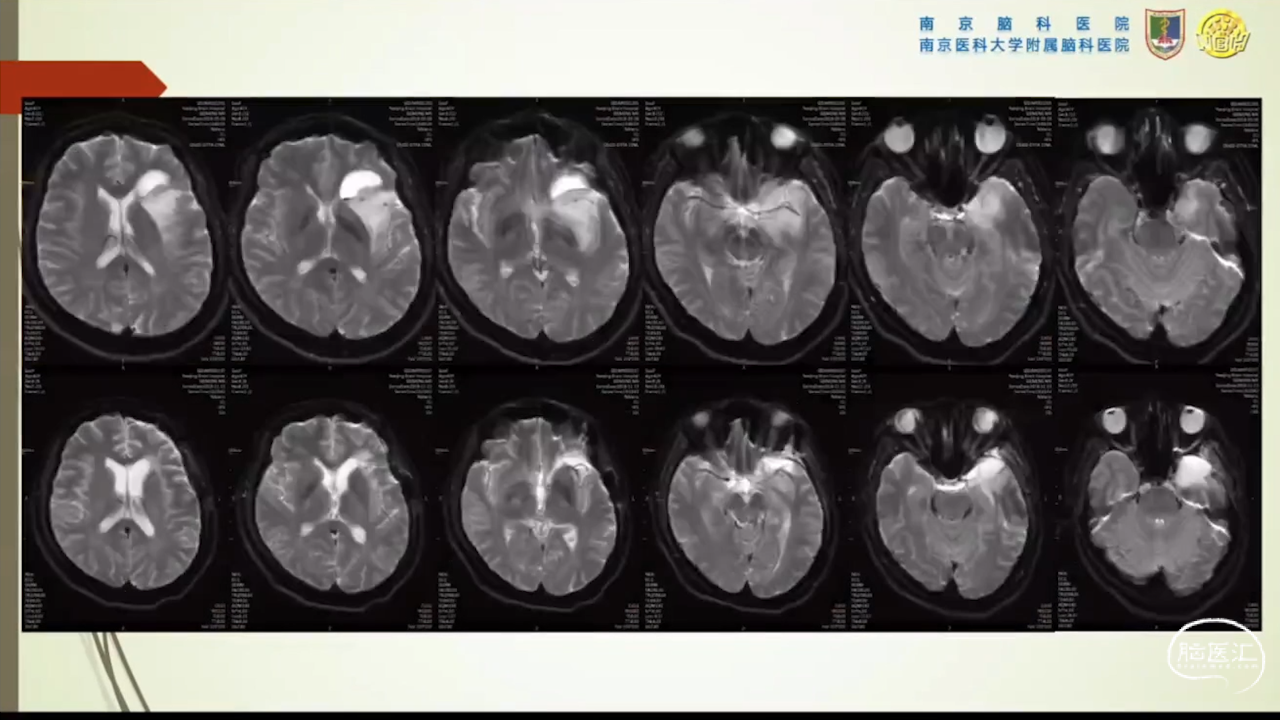

胶质瘤是发病率最高的颅内肿瘤(约占44.69%),岛叶是神经胶质瘤的好发部位,大约有25%的低级别胶质瘤及10%的高级别胶质瘤发生在岛叶,大多数岛叶胶质瘤为低级别胶质瘤。岛叶在调节内脏感觉运动、控制心血管交感活性、传入躯体感觉中均起重要作用。它也参与了痛觉的传递、运动规划、自主性吞咽、味觉、听觉、前庭功能、情绪、认知能力和语言能力。因为岛叶解剖结构复杂,并覆盖有高级语言皮层、白质束及重要的血管结构,故岛叶部位的手术难度极大。

会议内容截图